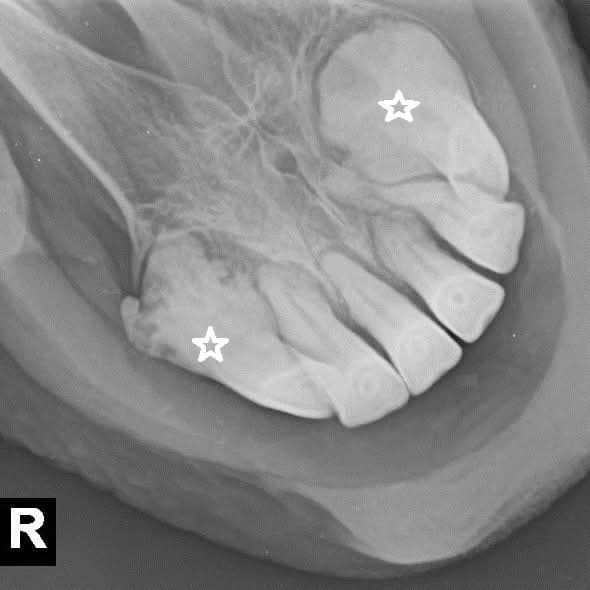

Gallery

I Nostri Lavori

Una selezione di casi clinici e momenti della nostra attività professionale